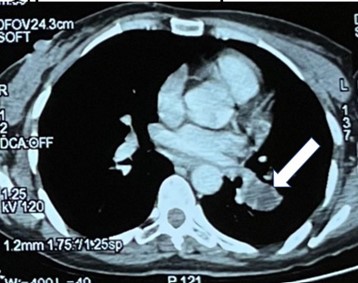

A lumbar puncture could not be performed due to the mass effect observed on the control imaging. The multiple nature of the strokes suggested an embolic origin. A tumor-related cause was considered, given the history of uterine bleeding. Among the indicated tumor markers, β-hCG levels were elevated (>15,000 mIU/mL with normal range <100 mIU/mL), increasing to 44,574 mIU/mL after 5 days. Thoraco-abdomino- pelvic computed tomography (CT) revealed the presence of a hypodense and heterodense endoluminal content at the level of both the left lower lobar artery and the left lower pulmonary vein without involvement in other locations.

Figure 3: Thoracic CT scan revealing a transcissural process at the level of the left lower lobar artery.